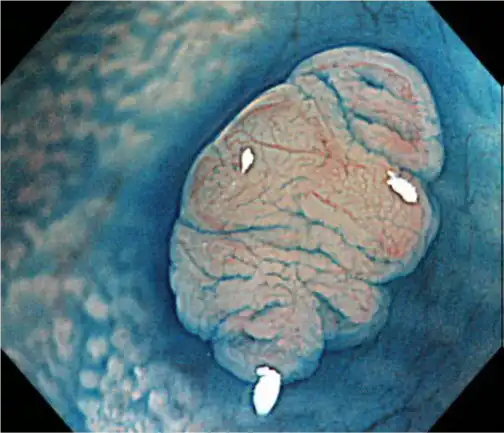

小直径的高光学放大

在保持纤细的外径的同时,PCF-H290ZL/I提供了110x*的光学放大倍率。高光学放大有助于病变的检测/诊断。

*使用高清液晶显示器OEV262H时

光学变焦 + NBI 光学变焦+ Dye spray